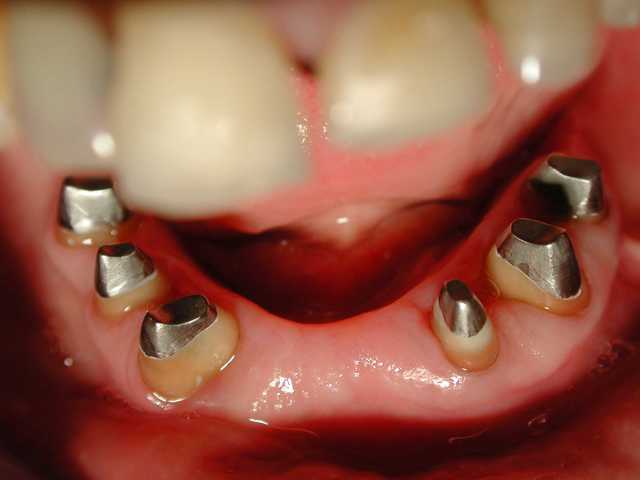

tu preferes quoi ? la photo 1 avec de belles reconstitution de 4 ans et bridge ,ou la photo 2+3 avec des ic haut et bas pour le meme cas refait ?

> tu preferes quoi ? la photo 1 avec de belles reconstitution de 4 ans et bridge

> ,ou la photo 2+3 avec des ic haut et bas pour le meme cas refait ?

Très beau sauvetage grâce à... des IC!

Et oui, il y a beaucoup plus de risque d'avoir des descellements, et des reprises de caries de ce genre, à cause d'un manque de rigidité et ou de résistance mécanique du substrat non reconstitué, ou seulement un composite sans ancrage radiculaire...